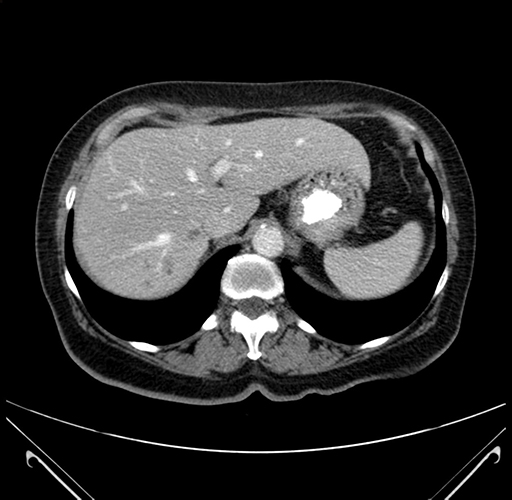

Pre-Chemo: Axial Venous